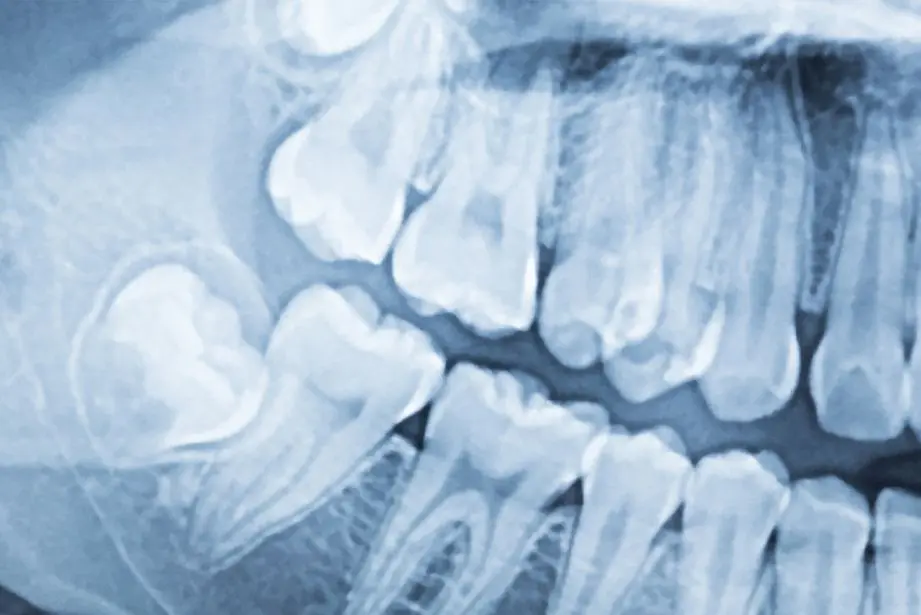

Sometimes an examination of the oral cavity alone does not tell us everything we need to know. What is visible to the eye can often be misleading, while the real problem may be hidden beneath the gum line, deep inside the tooth structures, or in the jawbone itself.

2D and 3D radiographic diagnostics leave no room for incorrect assessment and provide a true picture of the patient’s dental condition.

An orthopantomogram, or panoramic dental X-ray, is a panoramic image of the teeth that shows the current condition of the oral cavity and is taken before any dental procedure. Panoramic X-rays and CT scans are especially important when planning implant procedures and surgery in general.